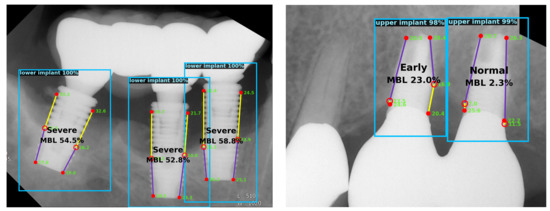

2.2.3. Bone Loss Ratio and Classification

3. Results